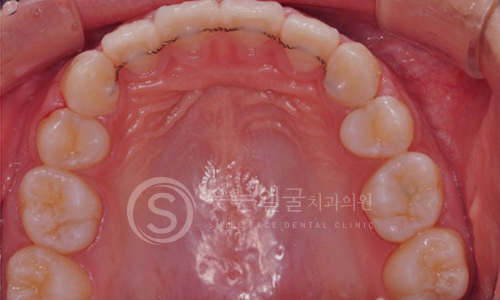

환자 개개인의 치아 형태와 구강 구조에 맞춘 맞춤형 크라운

제작으로, 자연스러운 기능과 심미성을 동시에 제공합니다.

또한 임플란트 10년 보증 시스템으로

장기간 안심하고 사용하실 수 있습니다.